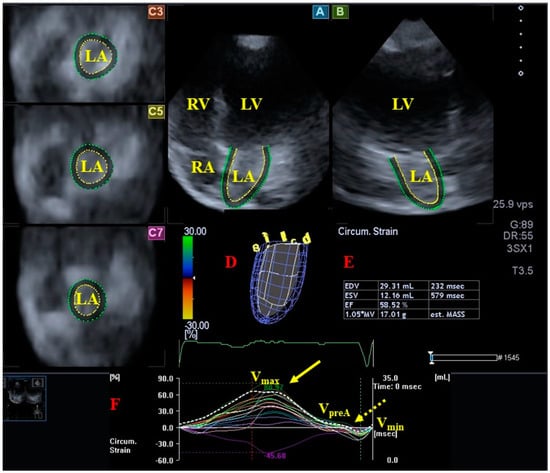

- Földeák, D.; Kormányos, Á.; Domsik, P.; Kalapos, A.; Piros, G.Á.; Ambrus, N.; Ajtay, Z.; Sepp, R.; Borbényi, Z.; Forster, T.; et al. Left atrial dysfunction in light-chain cardiac amyloidosis and hypertrophic cardiomyopathy—A comparative three-dimensional speckle-tracking echocardiographic analysis from the MAGYAR-Path Study. Rev. Port. Cardiol. 2017, 36, 905–913. [Google Scholar] [CrossRef] [PubMed]